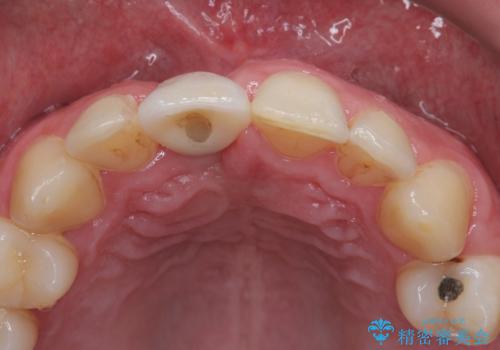

- 外れるたびに接着剤で応急処置を施してきた前歯のインプラント治療を希望して来院された患者様です。

以前から治療が必要であることは認識されていましたが、海外から日本に移住された1週間後に前歯が脱離したことで、当院でのインプラント治療を選択されました。

磨き残しなどによるプラークの付着が多いため、仮歯の用意と手術アポイントの調整を行っている間に口腔内のクリーニングなどを施し、環境がある程度改善されたのちに、抜歯即時インプラント埋入、即時荷重(インプラント埋入時に仮歯の装着)の予定で治療を行うこととしました。

度重なる脱離により、表側の炎症が非常に強くなっており、歯を支える骨が失われている状態でした。

そのため、現在の位置よりも歯と歯肉の位置が退縮する方向に移動する可能性があり、前歯2本の歯肉位置が大きくずれることとなるため、本人との相談のうえ、天然歯が萌えているような歯肉状態とはならないものの、2本の段差が少ない状態にて治療を終えることとなりました。